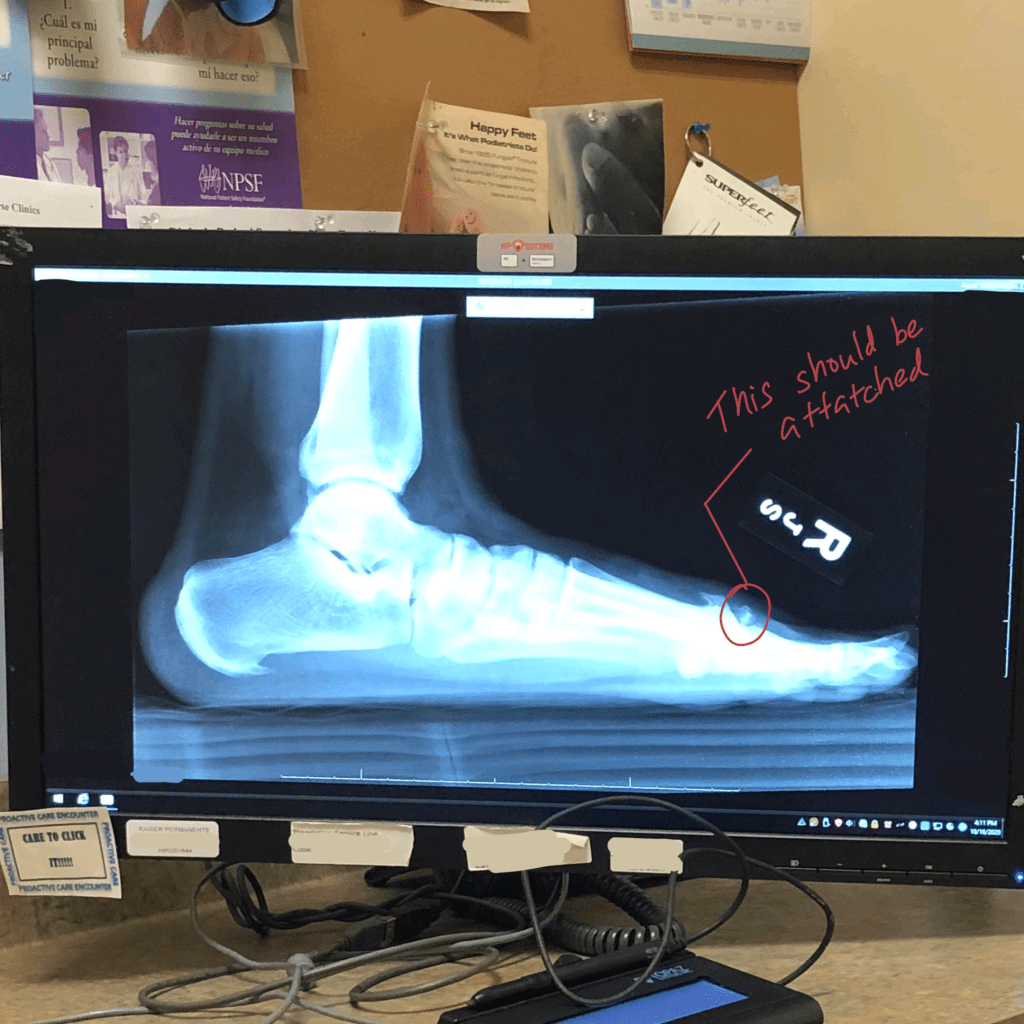

A tele-medicine appointment sent me to get an x-ray of my feet, and then a standing x-ray revealed that I did not have a bunion at all, rather I had this bone spur, this floating fragment of bone, and arthritis.